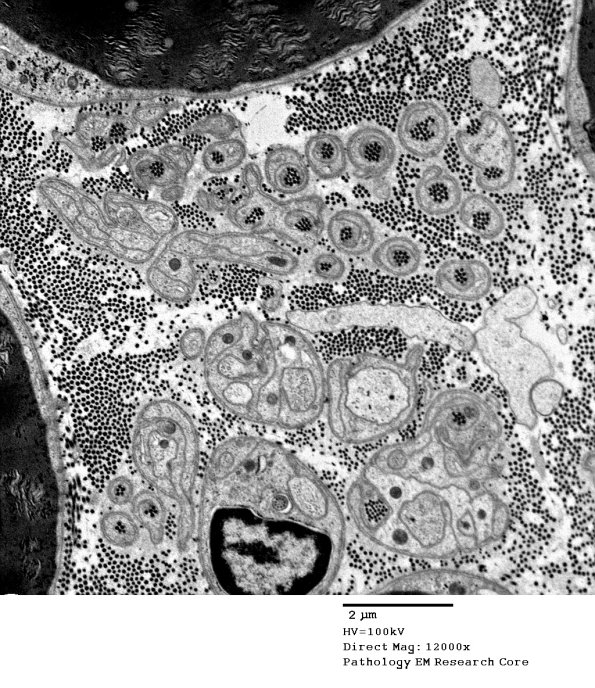

Washington University Experience | PERIPHERAL NEUROPATHY | 4 AXONAL DEGENERATION | 3 Electron Microscopy | 5D1 Collagen Pockets, unmyelinated (Case 25) EM 077 - Copy

5D1-4 Additional examples of collagen pockets signifying substantial numbers of lost unmyelinated axons.